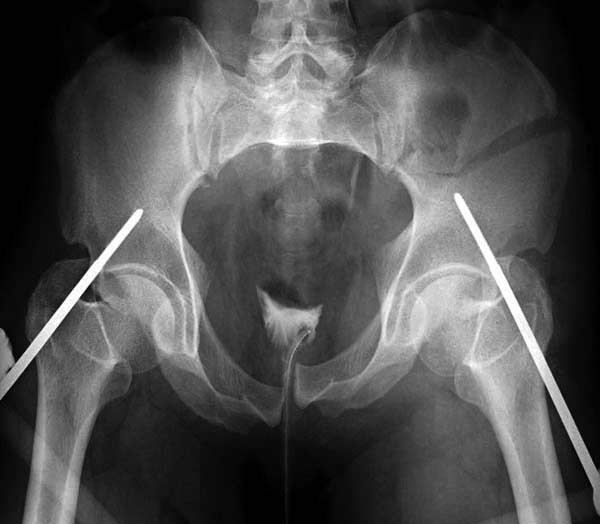

Здесь представлен случай 38 летнего больного (падение с высоты 9 метров) с нарушением тазового кольца. При поступлении для стабилизации передне-нижний аппарат наружной фиксации и на 6й день, вчера, операция из двух доступов.

Представлены снимки техники проведения стержней. Через место прикрепления прямой мышцы в Inferior Iliac Spine в направления вырезки создается жесткость. Weber clamp изнутри таза для репозиции, и фиксация после репозиции перелома крыла подвздошной кости. Наружный аппарат удален, нагрузка предполагается через два месяца.